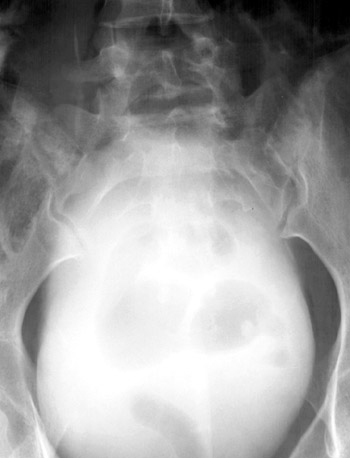

AP view of pelvis | |